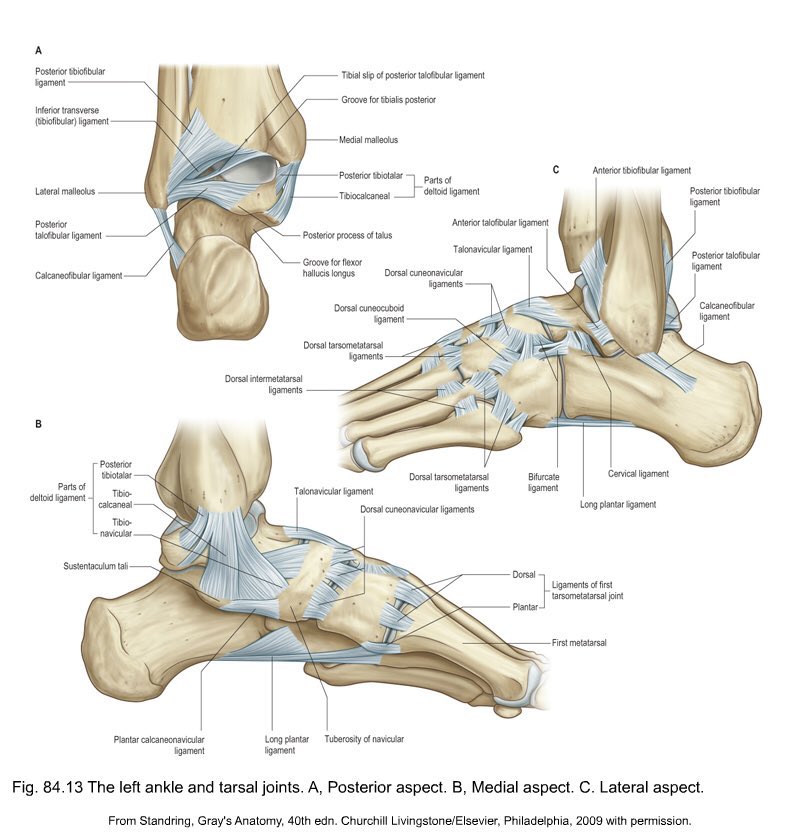

ويعتبر الكاحل واحدة من أكثر المفاصل تعقيداً من الناحية التشريحية وفِي هذه الصورة أربطة القدم من الجهة الداخلية والخارجية والخلفية. (٢)